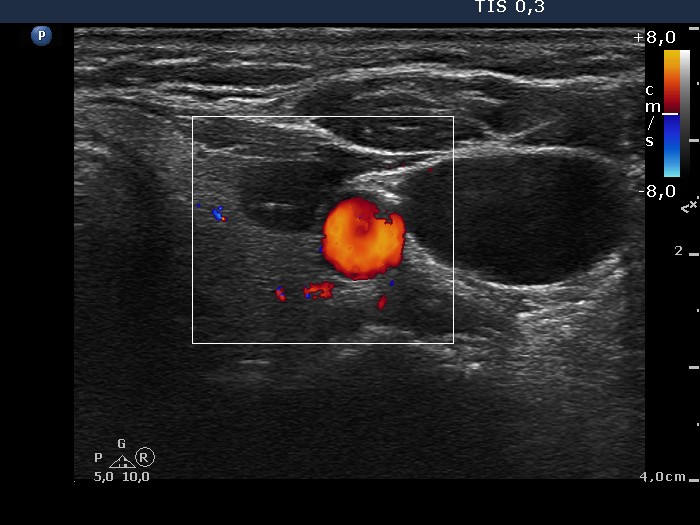

Lymphocytic thyroiditis - case 1365 (ultrasonographic picture 7)

Left lobe, transverse scan, color Doppler mode. The vascularization is decreased.